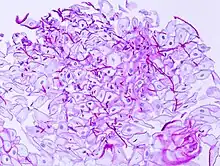

In most cases, the diagnosis is established based on response to therapy. Patients in whom esophageal candidiasis is suspected should receive a brief course of antifungal therapy with fluconazole. If the infection resolves after treatment with fluconazole, then the diagnosis of esophageal candidiasis is made and no further investigation is needed. However, if the infection persists or if there are other factors involved which may warrant further investigation, then patient will undergo an esophagogastroduodenoscopy if it is safe to do so. Endoscopy often reveals classic diffuse raised plaques that characteristically can be removed from the mucosa by the endoscope. Brushing or biopsy of the plaques shows yeast and pseudohyphae by histology that are characteristic of Candida species.

Esophageal candidiasis stained by periodic acid-Schiff procedure -

Esophageal candidiasis stained by periodic acid-Schiff procedure